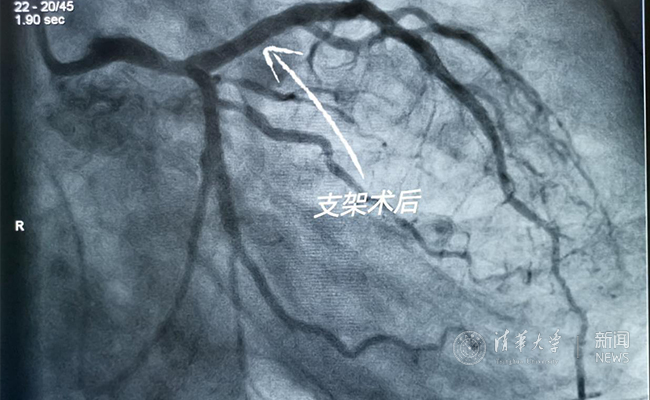

2019.05国产冠脉生物可吸收支架在米兰milan官方网站第一附属医院正式启用

作为北京地区首家正式引入国产冠脉生物可吸收支架单位,5月20日,米兰milan官方网站第一附属医院(北京华信医院)心脏中心主任苗立夫团队顺利完成该院首例生物可吸收支架植入。